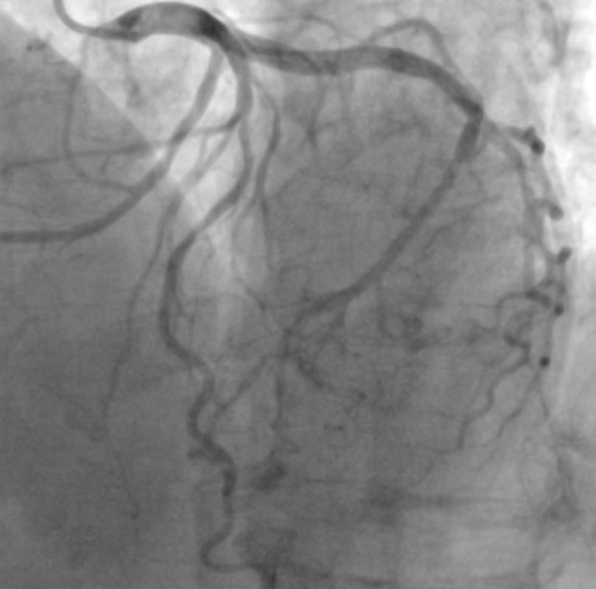

该患者因右侧桡动脉搏动较弱,本次手术穿刺左侧桡动脉,术中造影提示前降支血管重度狭窄,严重影响心肌供血,这是导致该患者频繁胸痛的罪魁祸首。经充分评估,徐亚伟教授决定应用ETcath 200介入手术机器人通过隔室操作为其进行冠状动脉介入治疗。

徐亚伟教授应用ETcath 200介入机器人对指引导管进行精准调整,使其到达冠状动脉口部,建立器械输送通路,并使用机器人的多种模式操作导丝,避免导丝进入分支,顺利将指引导丝推送至病变远端,应用机器人循导丝推送IVUS进行评估,测得管腔面积仅剩余2.31mm²。

造影图像